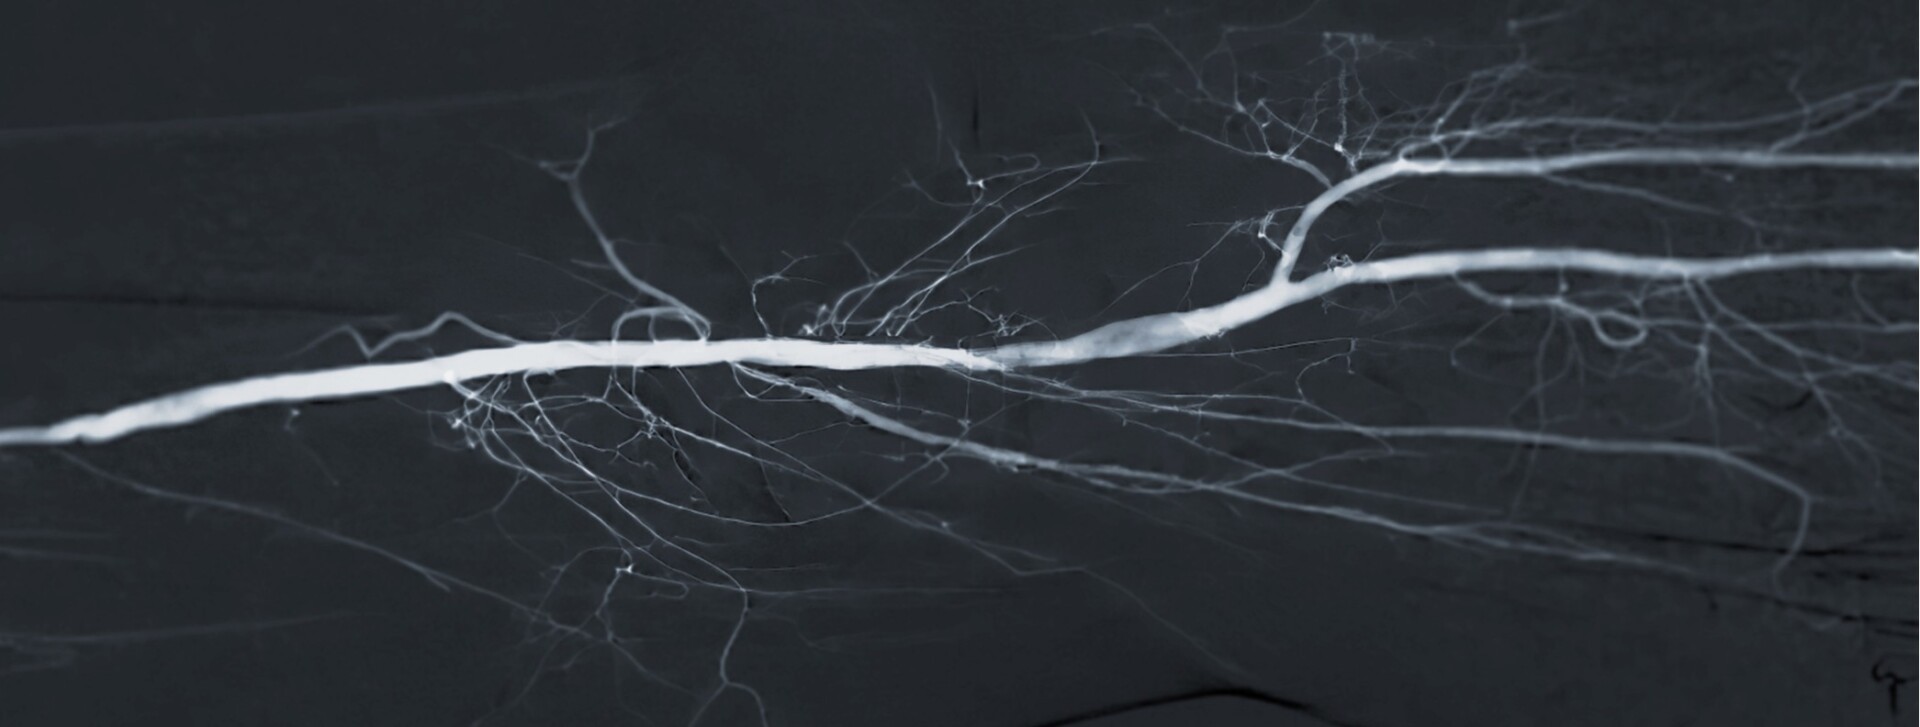

Behandling med medikamentbelagte ballonger (DCB) er en minimal-invasiv behandling av arterielle innsnevringer

Cardionovums Legflow og Aperto er medikamentbelagte ballonger (DCB) utviklet for effektiv behandling av arterielle innsnevringer. Legflow er spesielt designet for perifere kar, som femoropopliteale arterier, mens Aperto er optimalisert for bruk i dialysefistler og shunter. Begge ballongene kombinerer mekanisk utvidelse av karet med lokal levering av legemiddel som hemmer cellevekst, og bidrar dermed til å redusere risikoen for restenose og forlenge behandlingseffekten.

Safepax er Cardionovums innovative løsning for behandling av arterielle innsnevringer. Denne unike teknologien reduserer risikoen for legemiddeltap under innføring og manipulasjon, og sikrer at virkestoffet frigjøres målrettet først når ballongen blåses opp på behandlingsstedet. I motsetning til tradisjonelle DCB-løsninger, hvor legemiddelet kan avsettes eller gå tapt før ballongen er på plass, gir Safepax mer presis dosering, bedre effekt og økt pasientsikkerhet.